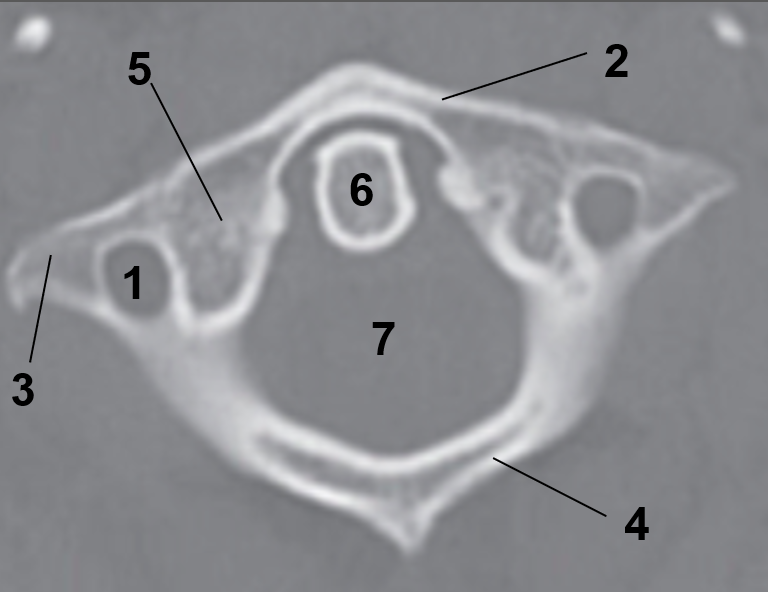

1?

Hard Palate

2?

Maxillary Bone

3?

Mandibular Rami

4?

Dens

5?

Transverse Foramen C1

6?

Spinal Cord

7?

Auricle

8?

Atlas